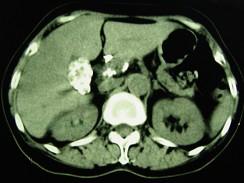

问题 女,66岁,右上腹痛,发热伴有黄疸两月余,消瘦、纳差,影像检查如图,最可能的诊断是()

选项 A.慢性胆囊炎及局灶性脂肪肝 B.胆囊壁钙化及肝血管瘤 C.胆囊癌肝转移 D.肝内胆管细胞癌 E.胆囊癌及原发性肝癌

答案 C